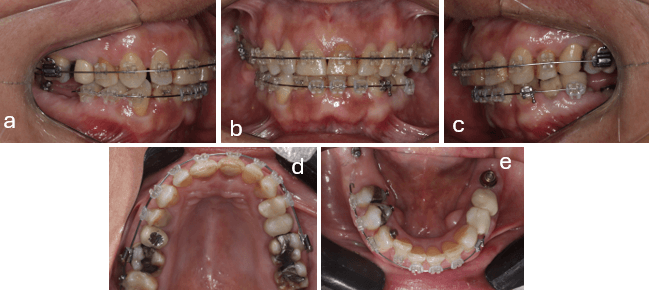

En el examen intraoral se observa Mal Oclusión de Clase II, división 2 subdivisión izquierda Tipo 2. Relación Molar ½ Clase II izquierda, Clase I derecha. Relación canina Clase I derecha, ½ Clase II izquierda. La línea media superior e inferior coincidentes. Overbite de 2 mm Overjet de 2 mm y mordida cruzada del 1.2 (fig. 2 a, b y c)

Arco superior con atresia y apiñamiento leve, molares 1.6 y 2.6 extruidos; 2.1 con cambio de coloración por tratamiento de endodoncia previo (Figura 2d), arco inferior forma triangular y apiñamiento moderado; corona del 4.6 defectuosa. Restauración oclusal de amalgama de 4.8 fracturada; dentición permanente con ausencia de piezas dentarias 3.6, 3.7 y 4.7 (fig. 2e).

Figura 2.- Fotos Intraorales Iniciales.

a) Lateral derecha b) Frontal c) Lateral izquierda d) Oclusal superior e) Oclusal inferior